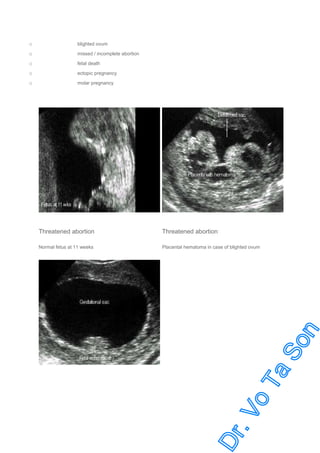

Threatened Abortion

Nonviable:

blighted ovum

missed / incomplete abortion

fetal death

ectopic pregnancy

molar pregnancy

Normal fetus at 11 weeks

Placental hematoma in case of blighted ovum